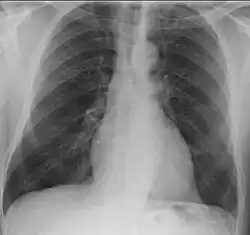

- Lungs: Pulmonary nodules (referred to as "coin lesions"), infiltrates (often interpreted as pneumonia), cavitary lesions, bleeding in the lungs causing a person to cough up blood, and rarely bronchial stenosis

- Lungs: Abnormal chest X-ray with nodules, infiltrates, or cavities